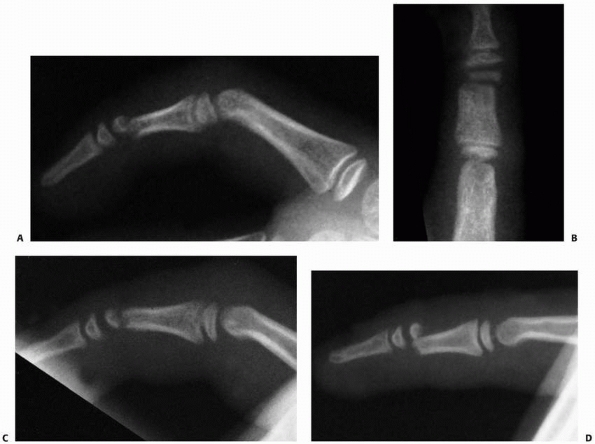

![]() |

FIGURE 8-36 A,B. A 16-year-old male sustained a dorsal S-H IV fracture of the middle phalanx. C,D.

Open reduction and internal screw fixation were accomplished through a dorsal approach. Radiographs show reduction of joint subluxation and fixation of fracture fragment. E,F. Postoperative extension and flexion with near normal motion. (Courtesy of Shriners Hospitals for Children, Philadelphia, PA.) |